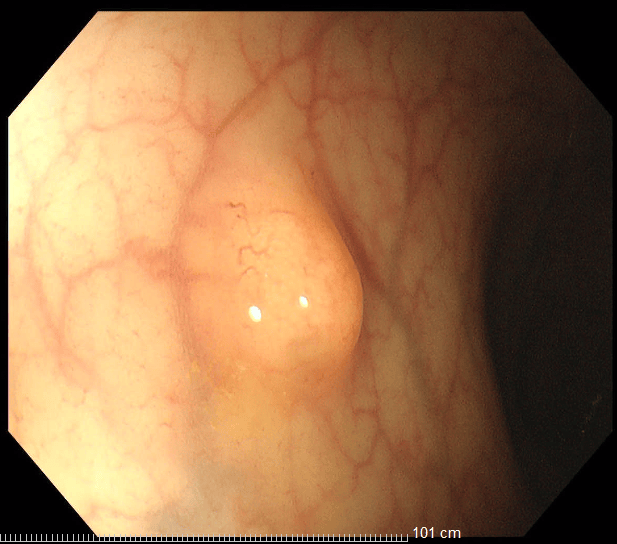

36歲的王先生在蘇州高新區人民醫院行胃腸鏡檢查時,發現直腸裡有1個息肉和2個黏膜下半球型隆起,表面光滑、顏色發黃,大小直徑約1.0cm,當時便做了超聲內鏡檢查,顯示2個隆起的腫物位於直腸黏膜下層,可能是神經內分泌腫瘤,1個粘膜層隆起的息肉可能是腺瘤腫瘤。消化科團隊立即為王先生進行了腸鏡下黏膜剝離術切除了2個粘膜下腫物,同時進行了腸鏡下粘膜切除術解決了1個腺瘤樣息肉,術後病理顯示:2個是神經內分泌瘤NET G1,切緣乾淨。1個管狀腺瘤伴低階別上皮內瘤變(屬於癌前病變),目前王先生恢復良好,已順利出院。

直腸神經內分泌瘤內鏡下治療的適應證包括腫瘤直徑<1 cm,侷限於黏膜或黏膜下層(T1期)的G1/G2級病變腫瘤。對直徑1-2cm的腫瘤,兼顧根治及功能保全,透過內鏡及影像學充分評估後選擇治療方式。內鏡下黏膜剝離術(ESD)是一項先進的內鏡下四級微創技術,醫生透過電刀,在內鏡下實現對胃腸道表淺病變的治癒性切除。